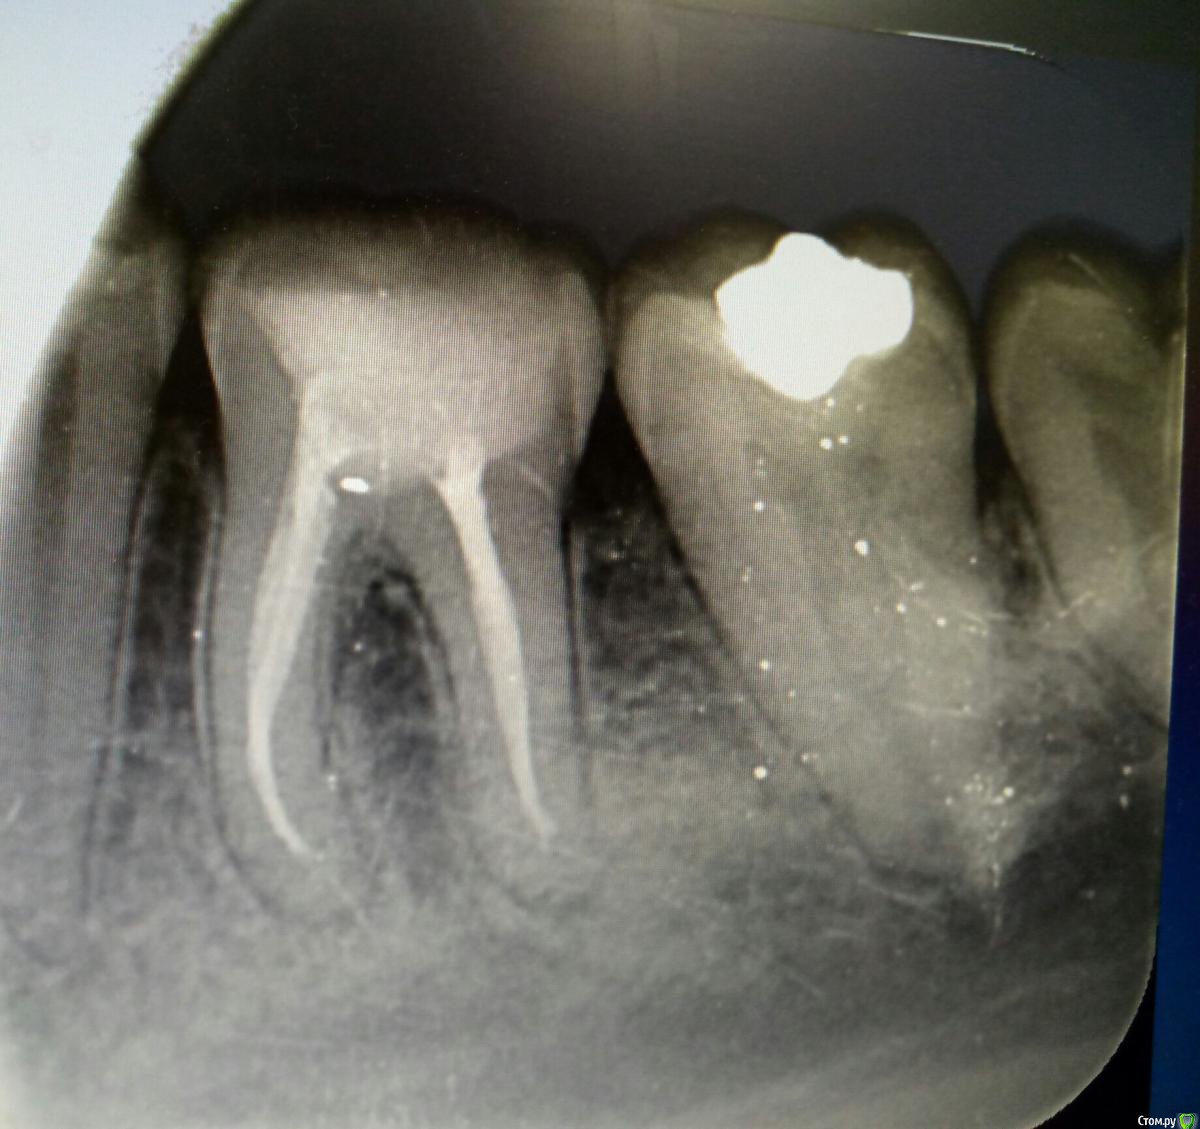

Verta Опубликовано 21 ноября, 2019 Поделиться Опубликовано 21 ноября, 2019 (изменено) Вечером разболелась половина лица, подумала на начинающийся гайморит или режущийся зуб мудрости. На 4 день боль локализовалась в нижней 6. Зуб пломбированный лет 15 назад, ранее не беспокоил, стал реагировать на холодное: рентген, пульпит. После наложения пасты реакция на холодное пропала, но при давлении на зуб сильная боль, также боль при давлении на десну под зубом только с внутренней стороны. Через 3 дня обратилась с болью- пасту переложили. После очередного приступа боли сделала КТ зуба, третий врач предположила, что это реакция на пасту. На лечении при прохождении одного канала была опять эта знакомая боль. Контрольный снимок показал правильно запломбированные каналы. И вот, спустя неделю, зуб сильно болит при накусывании, никаких изменений на дёснах нет, четыре врача не видят причины. Что делать? Снимки сделаны до лечения, ещё заложена паста Изменено 21 ноября, 2019 пользователем Verta Ссылка на комментарий

Verta Опубликовано 22 ноября, 2019 Автор Поделиться Опубликовано 22 ноября, 2019 Снимок Ссылка на комментарий